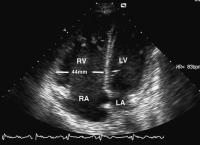

Abbildung 1: Vierkammerblick: Der rechte Ventrikel ist deutlich dilatiert (Querdurchmesser von 44 mm) und volumenbelastet; RA = rechter Vorhof, LA = linker Vorhof, LV = linker Ventrikel, RV = rechter Ventrikel